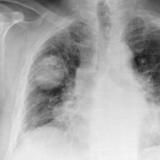

Hamartoma 1 PA